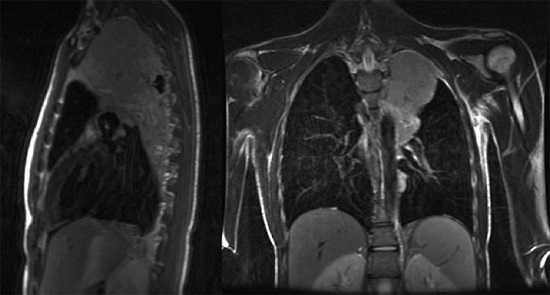

МРТ грудного отдела позвоночника в коронарной проекции

Магнитно-резонансная томография используется в дифференциальной диагностике заболеваний грудного отдела позвоночного столба в тех случаях, когда другие методы оказались малоэффективными. Данный вид аппаратного исследования безопасен для здоровья человека, не несет лучевой нагрузки и не требует хирургических манипуляций. Окончательная постановка диагноза во многом зависит от того, что показывает МРТ грудного отдела позвоночника.

В результате томографии врач получает серию послойных изображений спины, выполненных в аксиальной, сагиттальной и фронтальной проекциях. На основании полученных фото возможно построение 3D-модели изучаемой зоны.